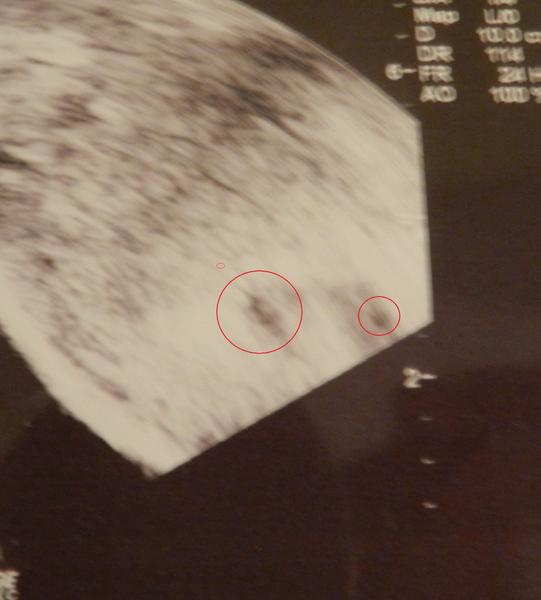

ahojky holky, nevím do jaké diskuze se s mým problémem vrtnou a ani nevím, jak se zakládá další, tak prosím o radu tady 🙂 Přidávám foto našich údajně dvojčat. foto bylo focena 6+3, ale dr mi řekl, že to odpovídá na 5týden. Jaký máte názor na ten plod? Myslím si, že kdyby měl lepší přístroj a mohl to víc přiblížit, že by stáří odpovídalo podle MS. a druhý váček se tam udělal během týdne a to se neví, jestli je to vytrácející se dvojče, nebo jestli se jen oplodnilo dýl. Jaký máte na fotku názory? Mohlo by být mimi starší, než tvrdí doktor? (mě přijde, že v tom jednom váčku už je docela větší kus bílý, tak že by to mohlo být už embrio) díky všem a pokud někdo dodá odkaz na lepší diskuzi, budu ráda 🙂

@miky00 ahojky mě se zdá,že to dvojče mizí bohužel ☹ a vůbec nevadí,že jsi o týden méně 🙂 a taky v tom druhém vidím asi plůdek 🙂 🙂 já taky toto těhu čekala dvojčátka,první týden na potvrzení těhu tam byl jen jeden váček,týden na to už 2 a další týden na to zase jeden a bylo už i srdíčko ♥ moc držím palečky aby ten jeden bojovníček byl tak jako náš Maty a bylo vše v naprostém pořádku... tato fotka je myslím s 4+6tt 😀